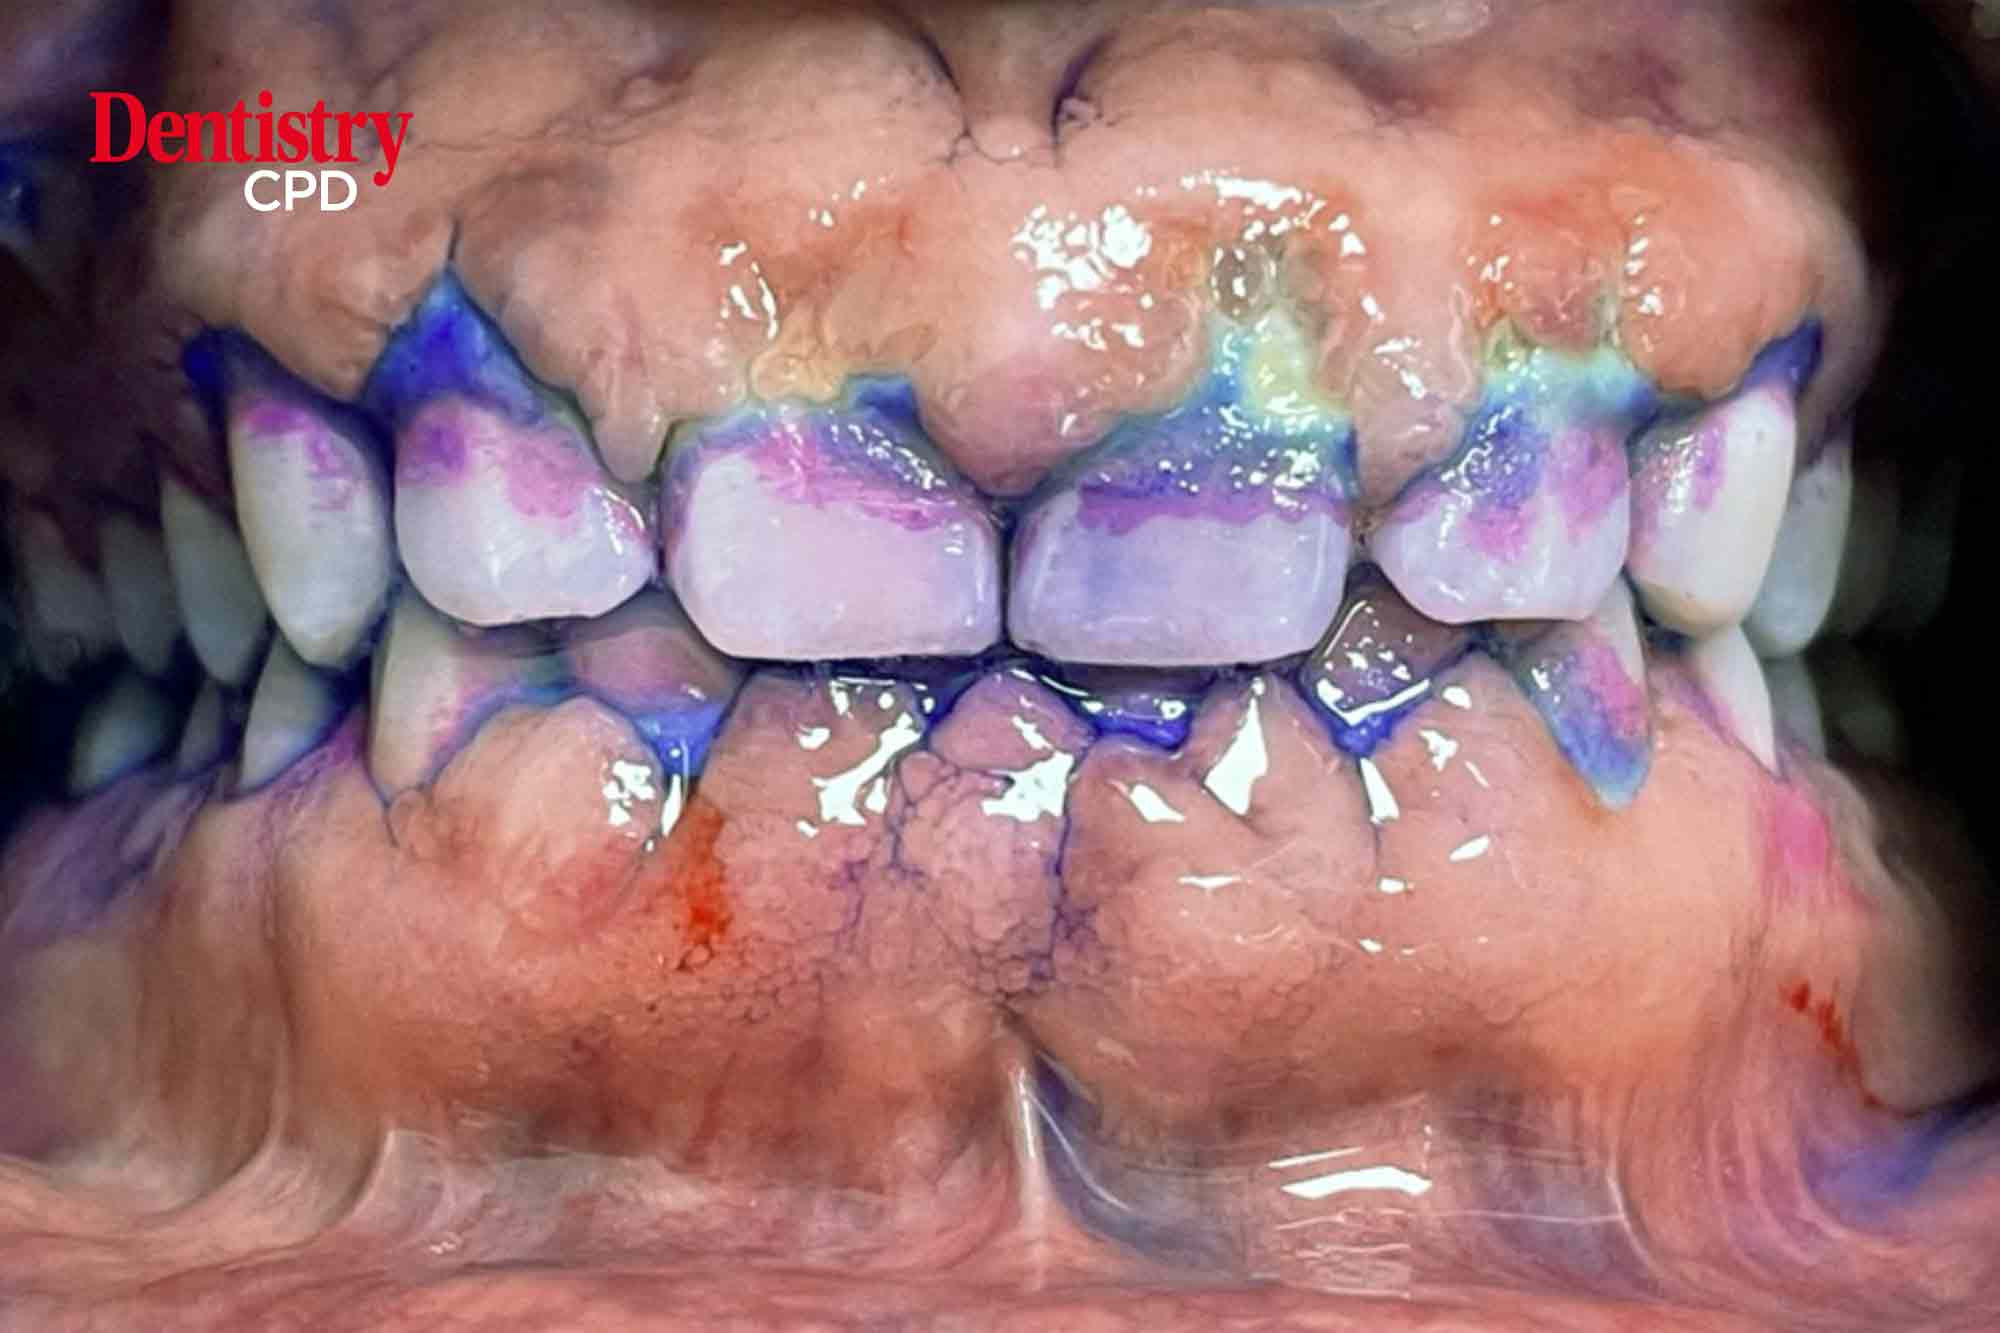

Rohini Pancholi-Bansal explores guided biofilm therapy (GBT), and asks if it’s a successful approach in the maintenance for a periodontal patient.

To provide a case study highlighting the use of guided biofilm therapy.